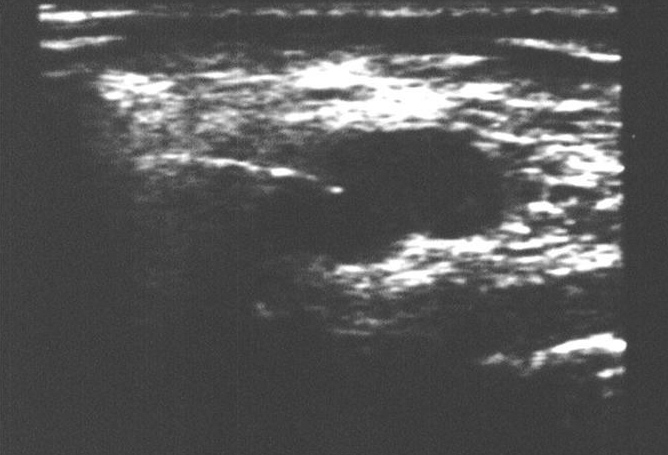

Micro-biopsie d’une adénopathie | Iconographie précédente | Retour cours | Index iconographique | Iconographie suivante |